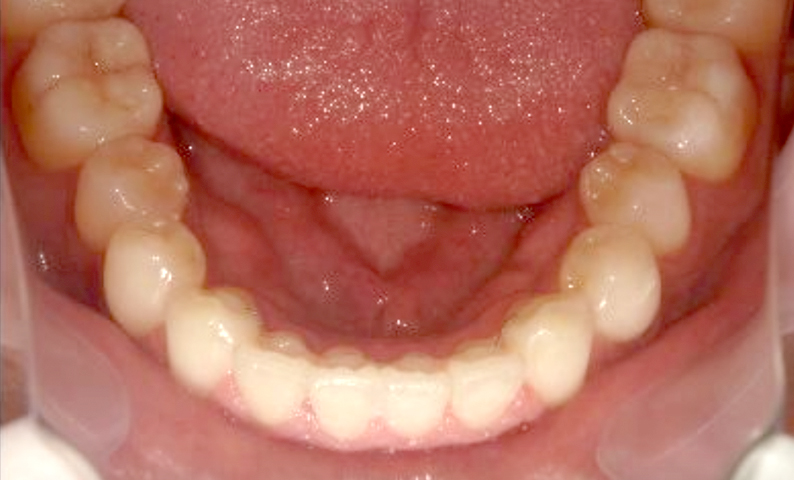

症例_004 下顎だけの部分矯正

治療期間:7ヶ月金額:24万円+税男性前歯のガタガタ下の前歯だけ

| Before | After |